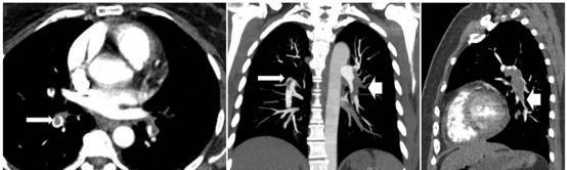

术后,排除手术相关因素后,结合患者的临床表现和术中症状,怀疑其发生了急性肺栓塞。进一步的诊断性检查明确了肺栓塞的诊断,结合CTPA(计算机断层扫描肺动脉造影)结果,显示大面积肺栓塞伴随右心室扩张和肺动脉高压。经胸超声心动图检查显示右心室负担加重,并伴有轻度的三尖瓣反流,肺动脉收缩压(PASP)达60mmHg。患者的D-二聚体水平显著升高,乳酸浓度也有所增加,这为肺栓塞的确诊提供了重要支持。

考虑到患者存在下肢深静脉血栓的背景,团队结合多学科会诊结果,决定采取抗凝治疗。具体措施包括静脉注射肝素5000IU,并持续泵入500IU/h,同时对患者进行严格的血流动力学监测。为了防止血栓进一步迁移,患者还接受了下腔静脉滤器置入术。在治疗方案的支持下,患者的病情逐渐稳定,术后第三天,肝素持续泵入停止,改为口服利伐沙班。经过5天的观察,患者顺利转出ICU。